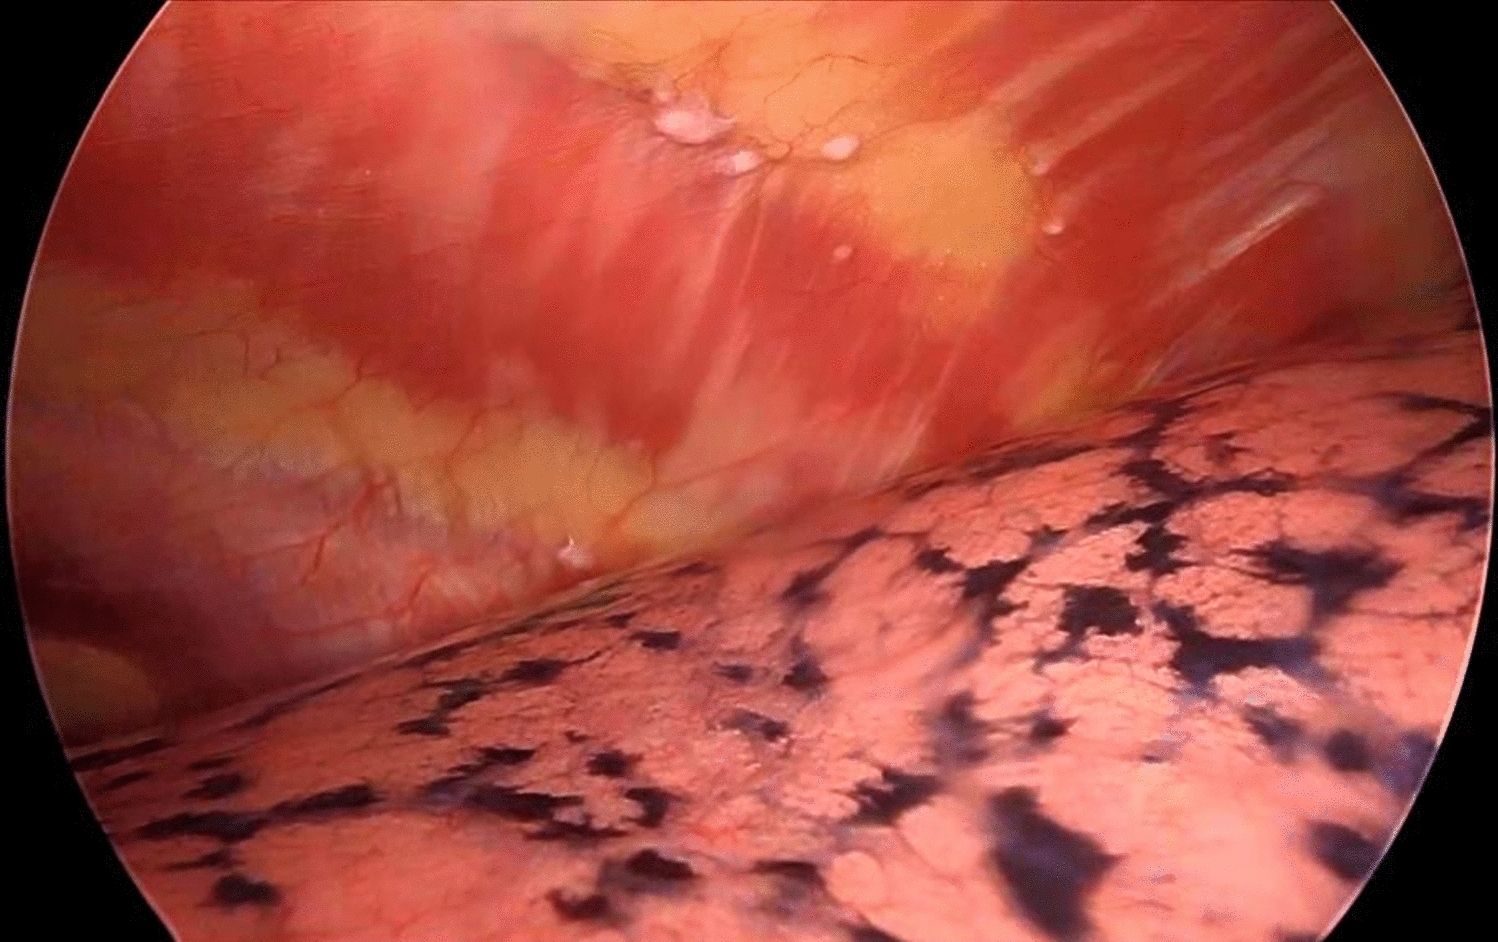

Three female patients with suspected ovarian tumors, based on clinical symptoms, imaging, and elevated CA-125 levels, were reviewed. Each patient underwent staging laparotomy, followed by histopathological examination of the resected masses. Surgical findings, including the presence of sulfur granules and Splendore-Hoeppli phenomenon, confirmed actinomycotic infection in all cases. Post-surgical treatment included prolonged antibiotic regimens tailored to each case.

Histopathology revealed that all patients had extensive actinomycotic infection, marked by inflammatory and fibrotic changes. Notably, none of the patients had a history of IUD use, which is atypical for pelvic actinomycosis cases. Following surgery and antibiotic treatment, all patients achieved full recovery without recurrence, underscoring the effectiveness of this combined approach.